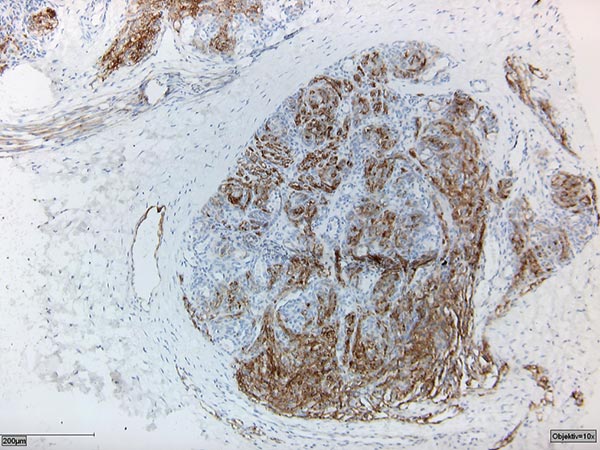

Histologie in Podoplaninfärbung (D2-40).

Die D2-40-Positivität für lymphatisches Endothel zusammen mit dem gefäßreichen Tumor bestätigten die Diagnose eines kaposiformen Hämangioendothelioms.